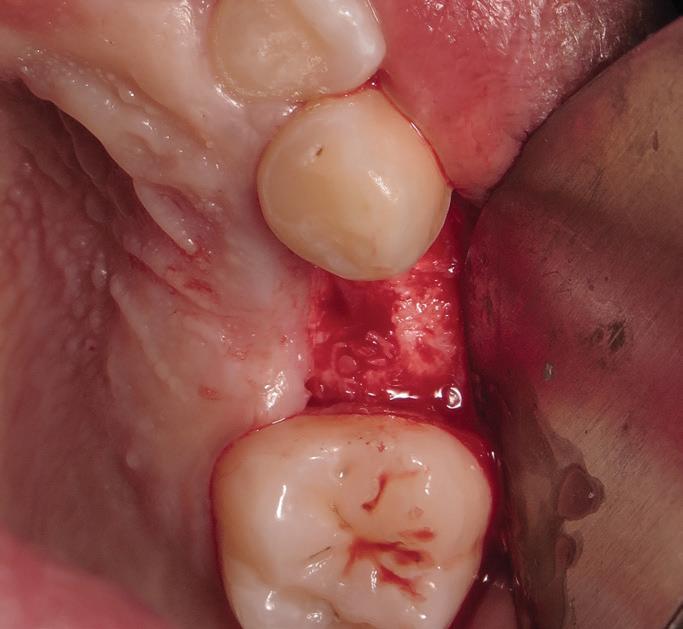

Tooth replacement from extraction to restoration. 3. Second-stage and impression procedures

The third part of this series reviews uncovering of implants that were buried in a 2-stage approach, provisionalization of the implant, and impression and scanning techniques.1 These techniques are all crucial for the final restorative outcome of the implant. The uncovering and second-stage procedures set the foundation for the shape and position of the soft tissue, which are very important esthetic factors. This information must also be properly transferred to the laboratory via a highly accurate impression so the laboratory has as much information as possible. If these steps are done properly, the result will be implant crowns that are easy to seat, biologically ideal, and esthetically pleasing.

Second-stage procedures